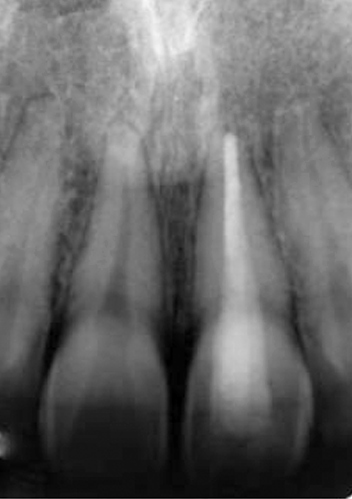

A imagem seguinte representa um caso desta área da medicina dentária: